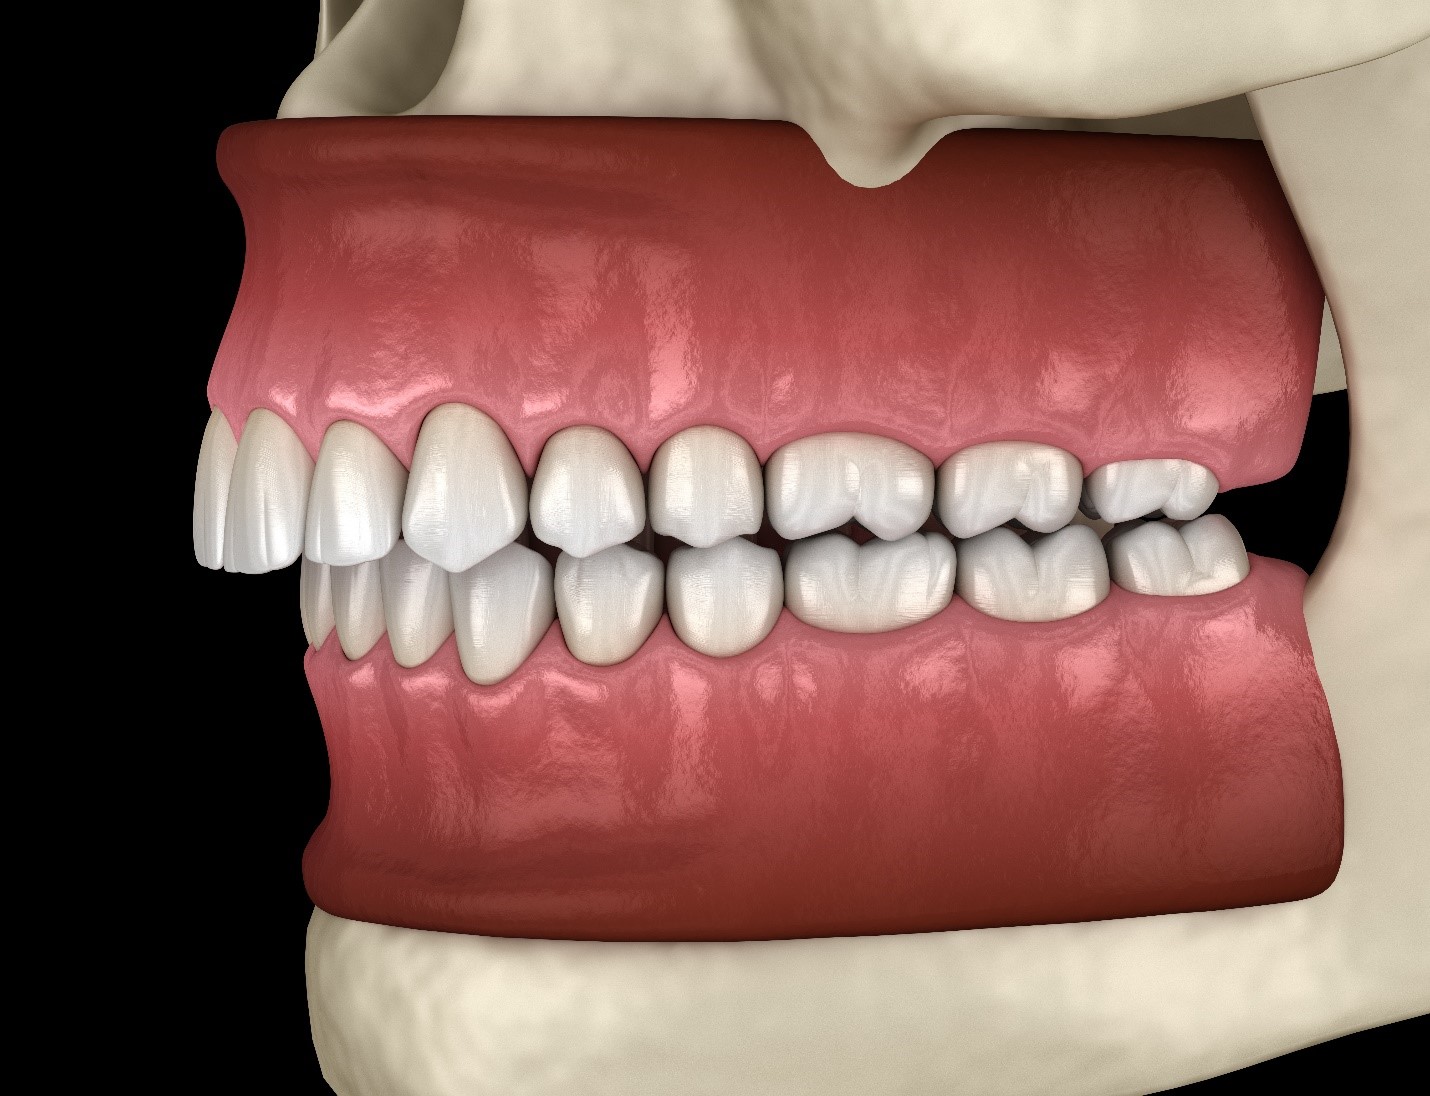

What Is An Overbite In Teeth And How Is It Corrected

What Is An Overbite In Teeth And How Is It Corrected